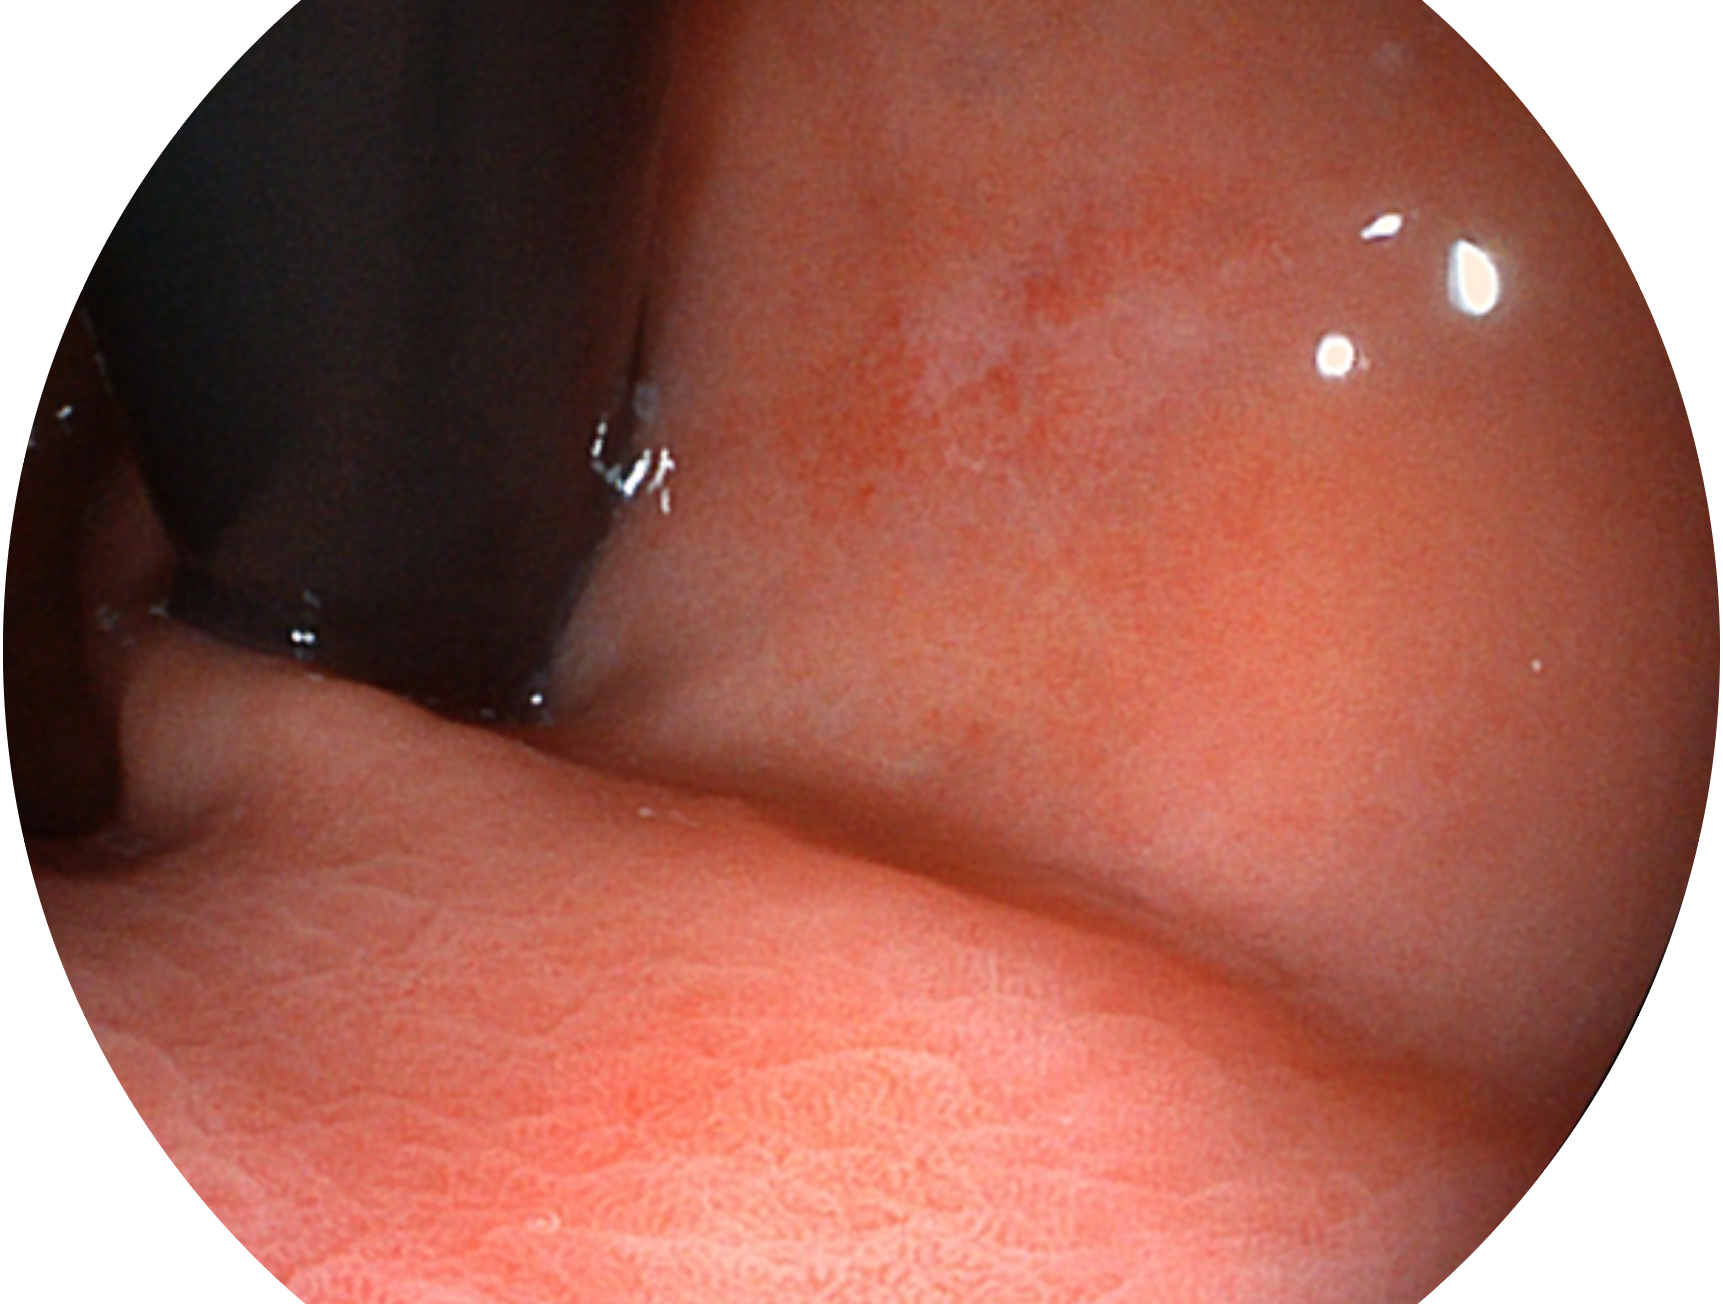

银河集团官网新开发的内镜染色技术,主要是基于多波长LED 光源的开发,VLS-55Q 四波长LED 光源是由四个不同颜色的LED光按照相应照明模式所规定的特定发光比例进行合束后形成,合束后形成的照明光的光谱由红光、绿光、蓝光及蓝紫光这四个不同的波段范围构成。具有更高光谱自由度,通过光谱比例的控制,实现了聚谱成像技术,英文全称为“Spectral Focused Imaging, SFI”,缩写为“SFI”和光电复合染色成像技术,英文全称为“Versatile Intelligent Staining Technology, VIST”,缩写为“VIST”。